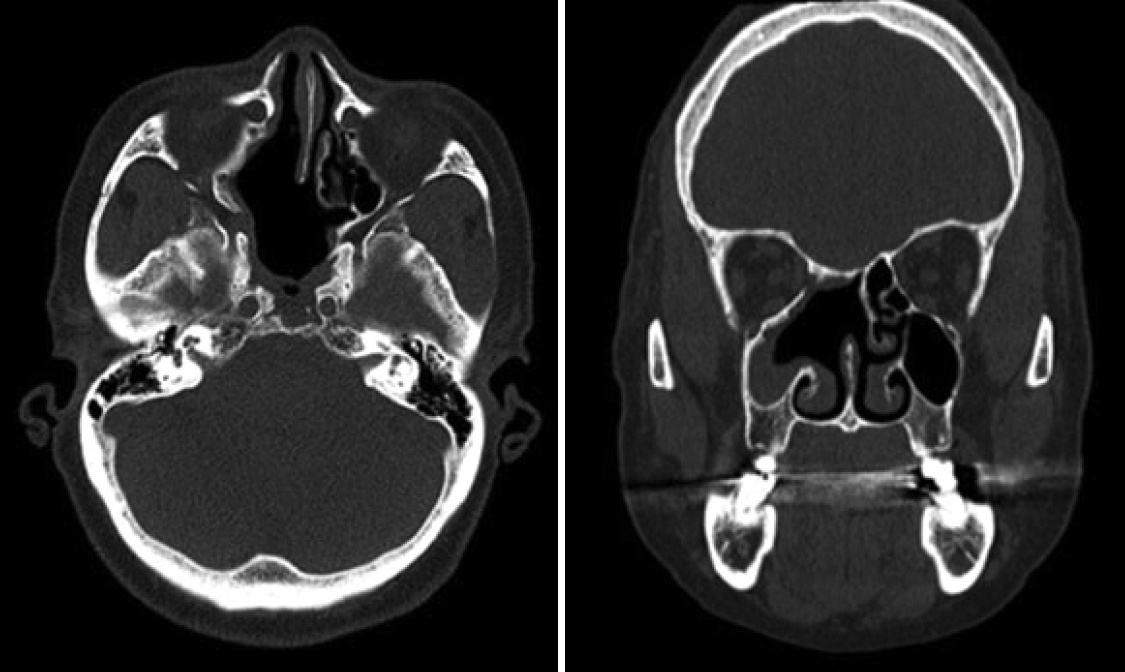

MRI scan findings were consistent with an intermediate signal on T1-weighted image (Fig. 2A), and heterogenous signal which includes presence of flow voids on T2-weighted image (Fig. 2B). Heterogenous enhancement was shown on contrast-enhanced T1-weighted image (Fig. 2C). Enhanced facial CT showed a 4 cm enhancing solid mass involving the right posterior nasal cavity, extending into the right ethmoid sinus and right sphenoid sinus, with evidence of bony erosion (Fig. 3). The left sphenoid sinus exhibited a non-enhancing mucoid density suggestive of sinusitis. Based on the imaging findings, the lesion was more consistent with an angiofibroma. Surgical treatment was decided accordingly.

Fig. 1.Endoscopic examination of right nasal cavity of the patient. A: Preoperative: a polypoid, whitish colored and solid mass found in the right nasal cavity, occupying between nasal septum and middle turbinate and extending to posterior nasal cavity. B: Postoperative 4 years: no residual mass or recurrence is found in the right sphenoid sinus. Fig. 2.Preoperative MRI images of the patient. A: T1-weighted image showed nasal cavity mass consistent with an intermediate signal. B: Heterogenous signal which includes presence of flow voids on T2-weighted image. C: Heterogenous enhancement was shown on contrast-enhanced T1-weighted image. Fig. 3.Preoperative enhanced facial CT images of the patient. A: Bony erosion of right lateral nasal wall by mass is shown in bone setting view. B: Both axial and coronal view show about 4 cm sized enhancing mass in right ethmoid sinus and sphenoid sinus. Fig. 4.Preoperative angiography. A: Through angiogram selected by right internal maxillary artery, hypervascular staining (red arrow) of right nasal cavity was shown. B: Hypervascular staining of right internal maxillary artery disappeared after embolization (blue arrow). Fig. 5.Microscopic features of permanent biopsy (hematoxylin and eosin stain, ×40). A: Sinonasal papilloma with inverted growth pattern. B: Various sizes of vascular spaces, ranging from dilated branching vessel to slit-like capillaries filled with fibrinous thrombin and edematous to collagenous stroma which indicates angiofibroma. REFERENCES2. Lisan Q, Laccourreye O, Bonfils P. Sinonasal inverted papilloma: from diagnosis to treatment. Eur Ann Otorhinolaryngol Head Neck Dis 2016;133(5):337-41.